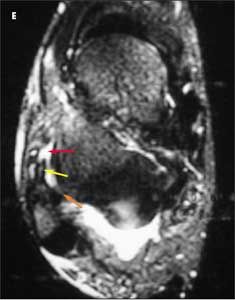

This patient has a grade 3 injury to the anterior talofibular ligament. In another axial T2-weighted image (E), fluid (yellow arrow) is visible in and around the course of the ligament (red arrow). This confirms that the disruption is acute. The posterior talofibular ligament appears normal and intact (E, orange arrow).

Patients with injuries of this ligament often do not seek medical attention, and it can be difficult to distinguish between acute and more remote injuries on imaging studies. Acute tenderness and fluid at the site of the disruption are 2 clues that can help identify an acute injury.

A coronal T1-weighted image shows thickening of the calcaneofibular ligament (

F,

arrow); however, the fibers of the ligament are intact, which indicates that the injury is microscopic (a grade 1 injury). On all the images, the lateral malleolus is normal and intact, which rules out fracture.